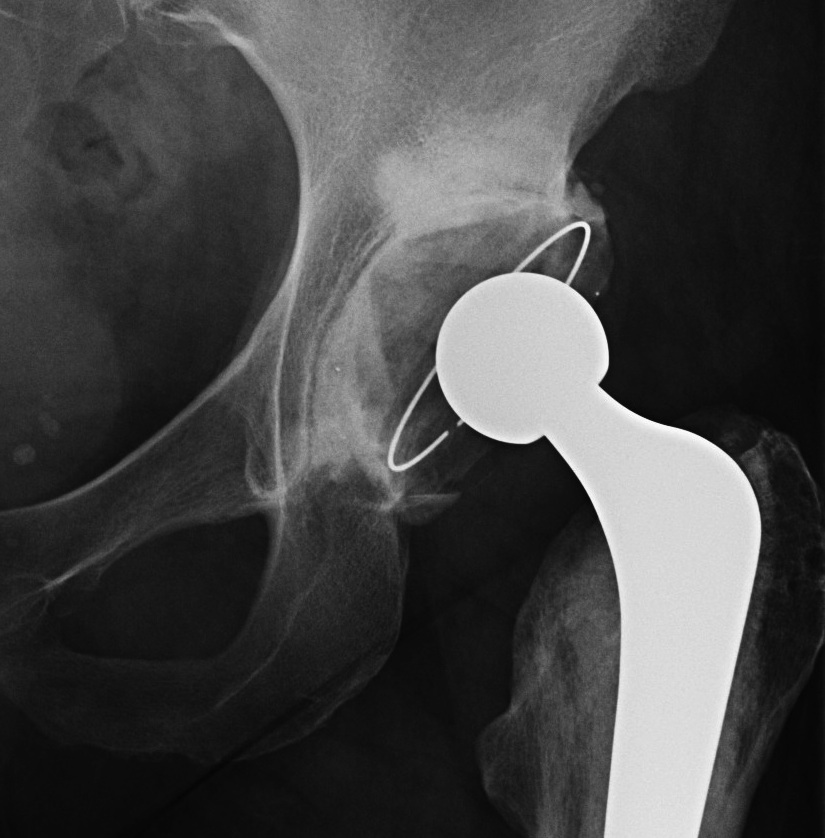

Zimmer ZCA all poly cup

Components

- all polyethylene

- spacers to ensure even cement mantle

- +/- flange to compress cement / prevent escape around cup

- metal insert to gauge position on xray